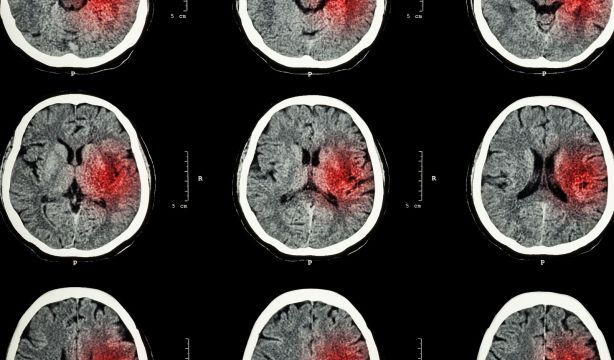

La Estrategia en Ictus del Sistema Nacional de Salud. Actualización 2024, recogida por la Sociedad Española de Cardiología no puede ser más contundente. En su introducción aclara: "El ictus es una de las enfermedades de mayor impacto mundial. Como el origen del término indica (golpe, ataque súbito y violento), implica un riesgo para la vida de millones de personas y es capaz de cambiarla en pocos minutos para siempre. Los datos son contundentes: es la segunda causa de muerte, la tercera causa de discapacidad, después de los accidentes neonatales (en niños) y cardiopatía isquémica (en adultos), y una de las principales causas de demencia en todo el mundo".

La incidencia por edad de ictus en personas más jóvenes (es decir, menos de 55 años) está aumentando tanto en los países de ingresos altos como en los de ingresos bajos y medios. Cada año, alrededor de 120.000 personas sufren un ictus en España y fallecen alrededor de 25.000 por esta enfermedad. La edad es uno de los factores de riesgo principales de esta enfermedad, por lo que se espera que la incidencia siga en aumento, dado el creciente envejecimiento que está experimentando la población. Pero el ictus no afecta únicamente a personas de edad más avanzada, ocurre en todos los grupos de edad, incluida la pediátrica y la de adolescencia. Según las proyecciones, se estima que para el año 2025 el número de casos anuales de ictus en Europa aumente a más de 1,5 millones. Y se prevé, también, que en el mundo una de cada cuatro personas lo sufrirá a lo largo de su vida.

El segundo avance publicado llega de la Universidad Simon Fraser (SFU, de sus siglas en inglés), en Canadá, y ha revelado cómo un tipo de daño cerebral indirecto pasado por alto contribuye a la discapacidad persistente después de un ictus y ofrece un nuevo camino hacia un posible tratamiento. El ensayo, que ha sido publicado en 'Proceedings of the National Academy of Sciences', muestra cómo el tálamo –una especie de centro de conexión que regula funciones como el lenguaje, la memoria, la atención y el movimiento– se ve afectado meses o años después de que una persona haya sufrido un ictus, aunque no haya sufrido daños directos.

Para el estudio, los investigadores registraron la actividad cerebral de 18 pacientes con ictus crónico y utilizaron modelos informáticos para comprender cómo esta actividad cerebral refleja una función anormal del tálamo en comparación con individuos sanos. Al estudiar la actividad cerebral y la anatomía de los supervivientes, los investigadores de la SFU afirman que parece haber una relación entre la cantidad de daño indirecto sufrido por el tálamo y el nivel de deterioro que experimenta un paciente.

Johnston explica que el tálamo se comunica ampliamente con el resto del cerebro a través de muchas conexiones largas, llamadas axones, lo que lo hace susceptible a daños indirectos. Cuando los axones se lesionan por un ictus en otras regiones del cerebro, el daño puede viajar a lo largo de la célula y dañar las neuronas del tálamo, lo que provoca que su función se vea afectada.

Este deterioro también tiene un efecto dominó al interrumpir las funciones que el tálamo ahora dañado normalmente regularía en otras partes no dañadas del cerebro. Si ciertos tratamientos, como medicamentos o estimulación cerebral, pudieran restaurar la función normal del tálamo o mitigar el impacto del daño que viaja al mismo y mantenerlo funcionando normalmente, los investigadores creen que se podrían aliviar algunos impactos a largo plazo del accidente cerebrovascular.